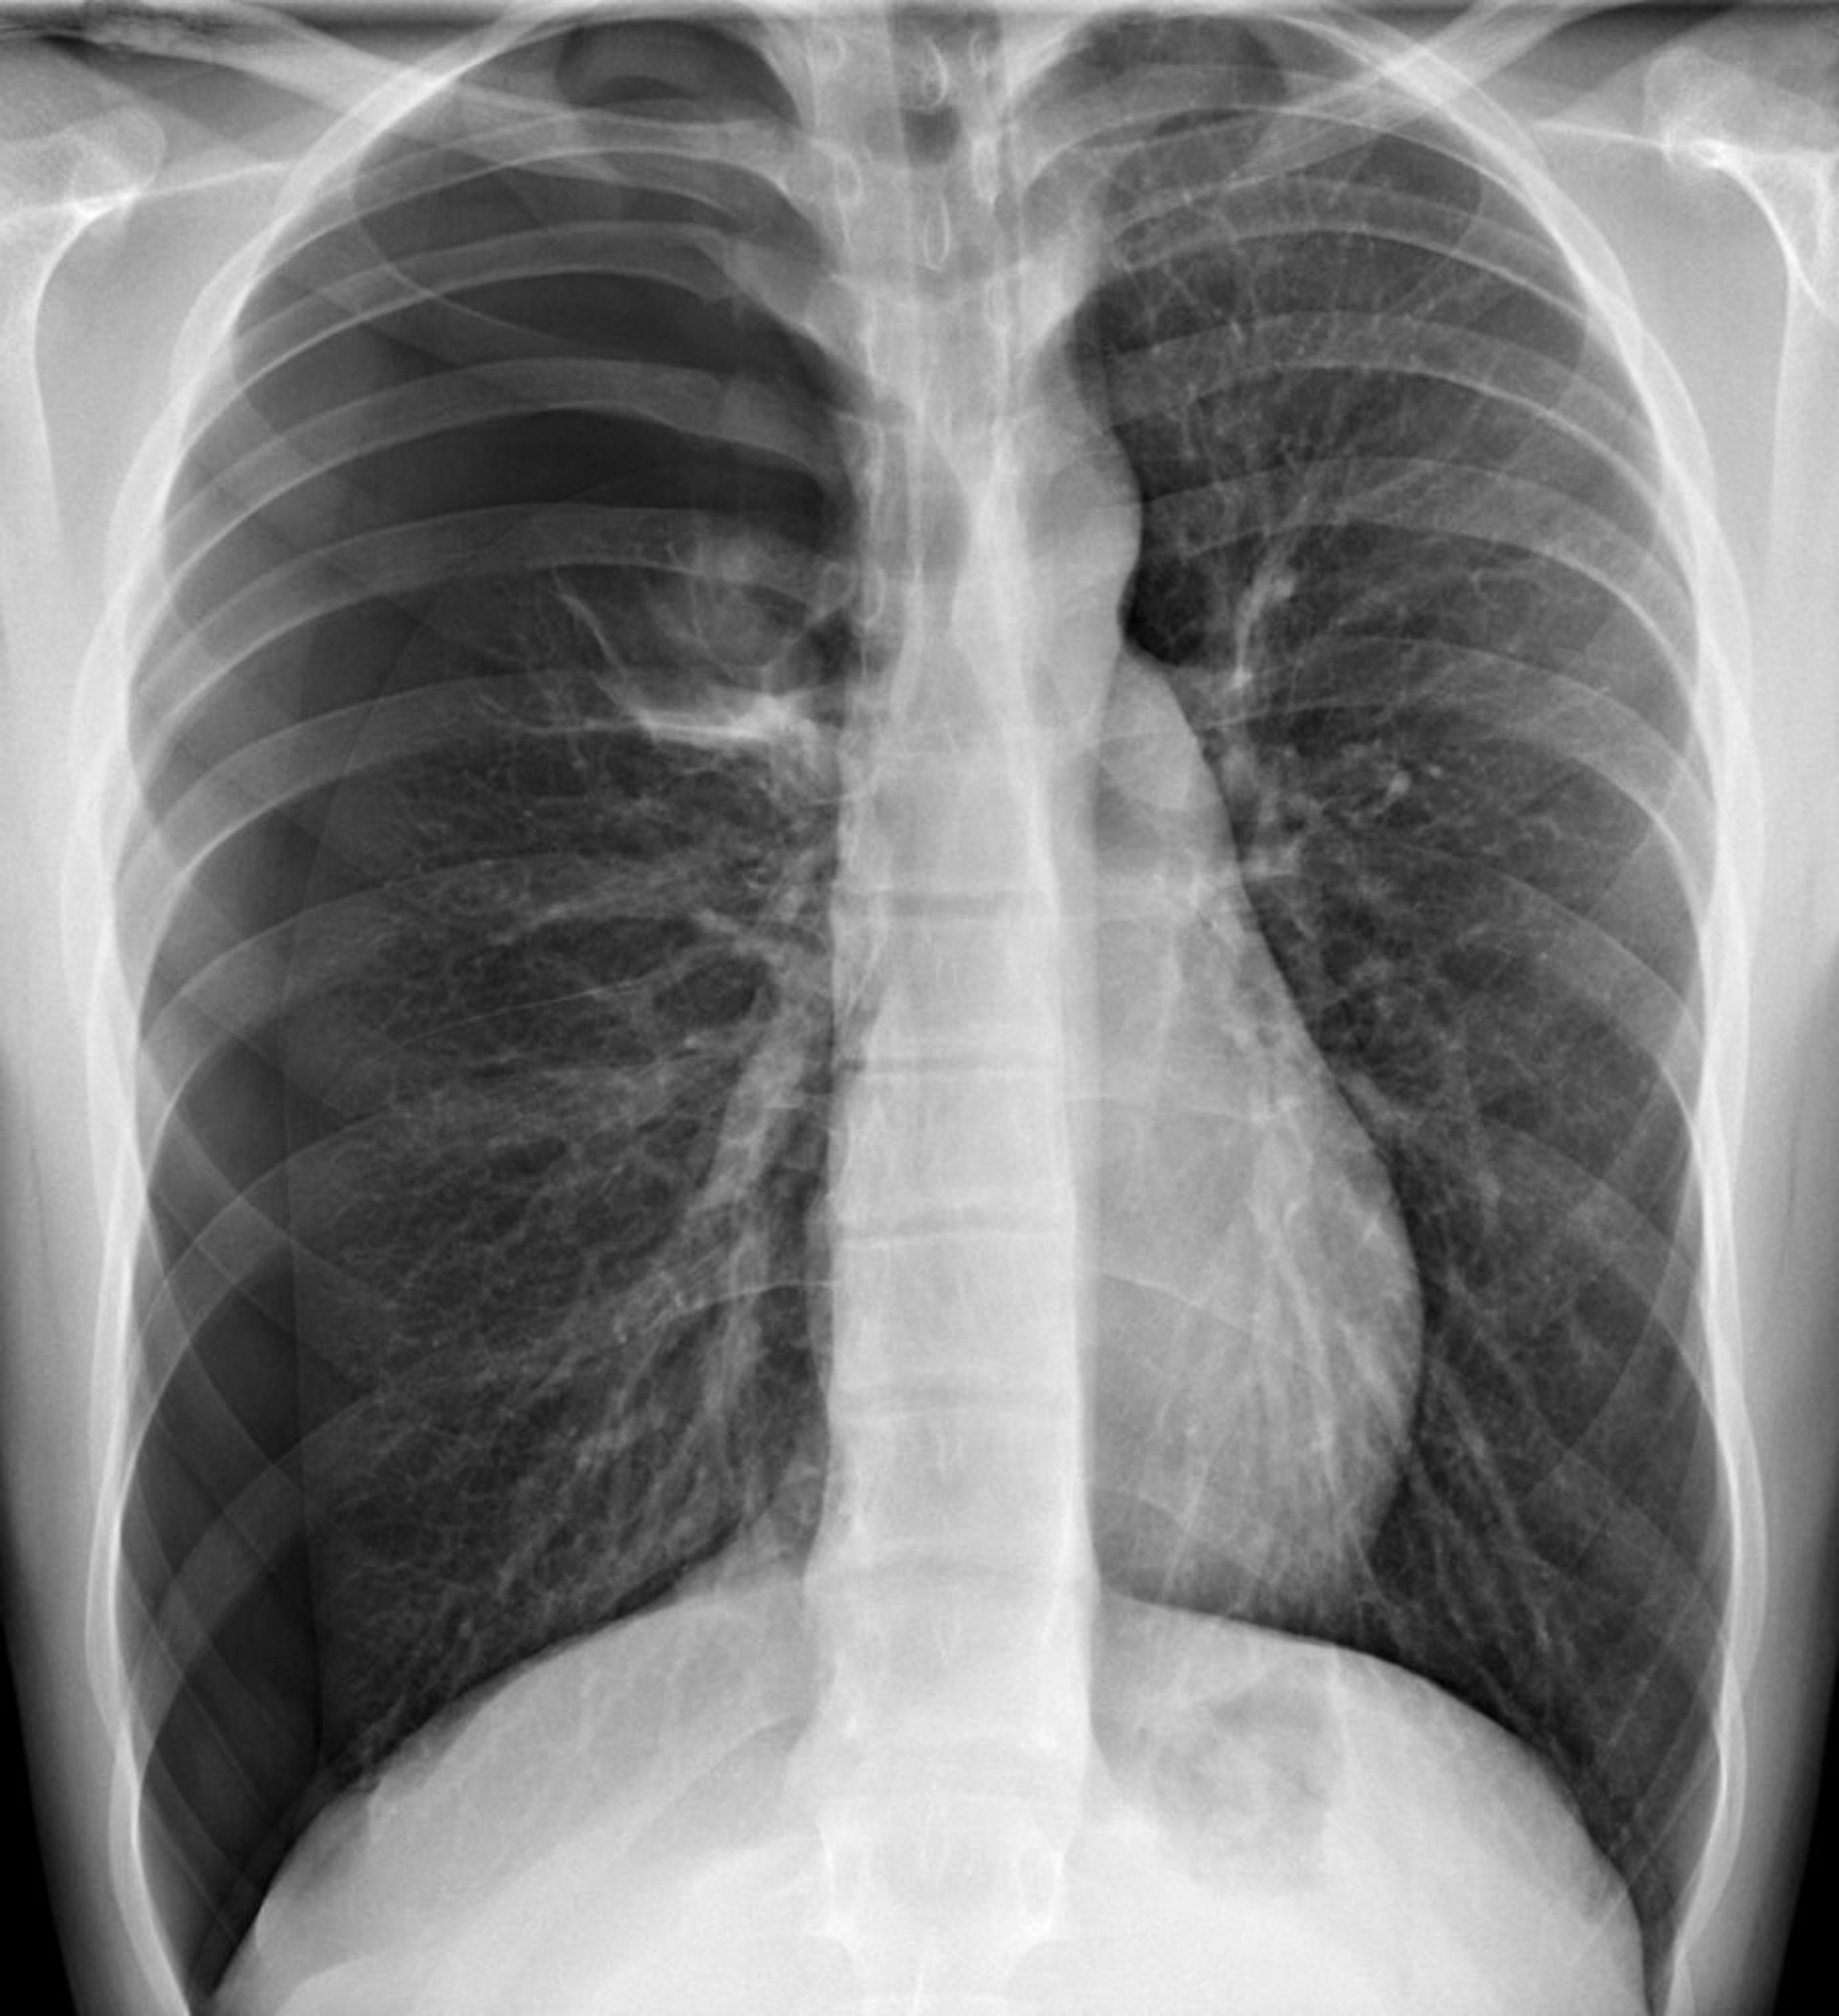

Напружений пневмоторакс

На цьому зображенні видно пневмоторакс у правій половині грудної клітки, де на периферії відсутній легеневий малюнок. Зсув серця та середостіння ліворуч може викликати фізіологічні зміни, характерні для напруженого пневмотораксу. Проте напружений пневмоторакс слід діагностувати на підставі клінічних даних, а очікувати рентгенологічного підтвердження.

DU CANE MEDICAL IMAGING LTD / НАУКОВА ФОТОБІБЛІОТЕКА